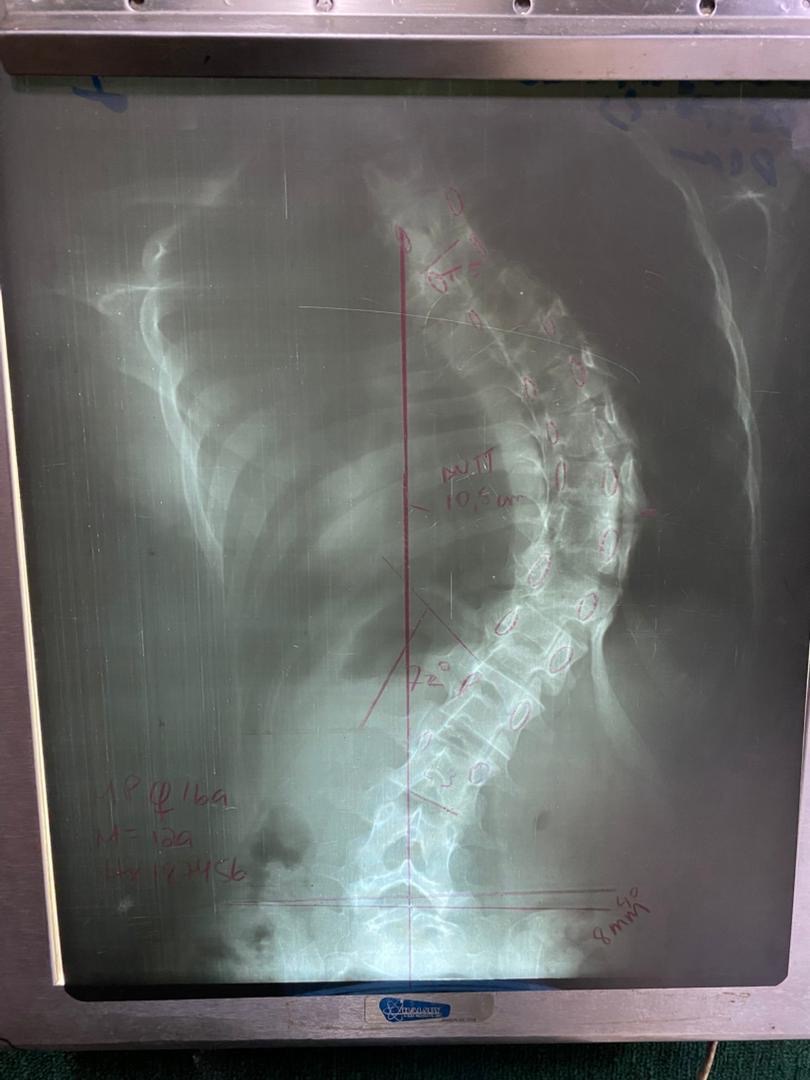

I'm Mariangel Chiquinquira Prado Corona, I'm 16 years old, I went to the consultation for presenting trunk deformity of months of evolution. In the clinical examination, asymmetry of shoulders, scapulae and waist triangle is observed. Adams test positive, right giba and left prominence. Menarchy: 12 years.

In panoramic X-ray of the spine, lumbar dorsal scoliotic curve pattern is observed

From T4 to L4 of 80°.

IDx: Idiopathic Scoliosis of the Adolescent